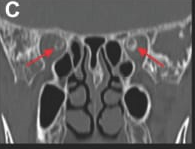

CT (bone window) – red arrows highlight optic sheath calcifications; green arrows show normal brain tissue.

Coronal CT – red arrows mark optic nerve sheath calcifications.